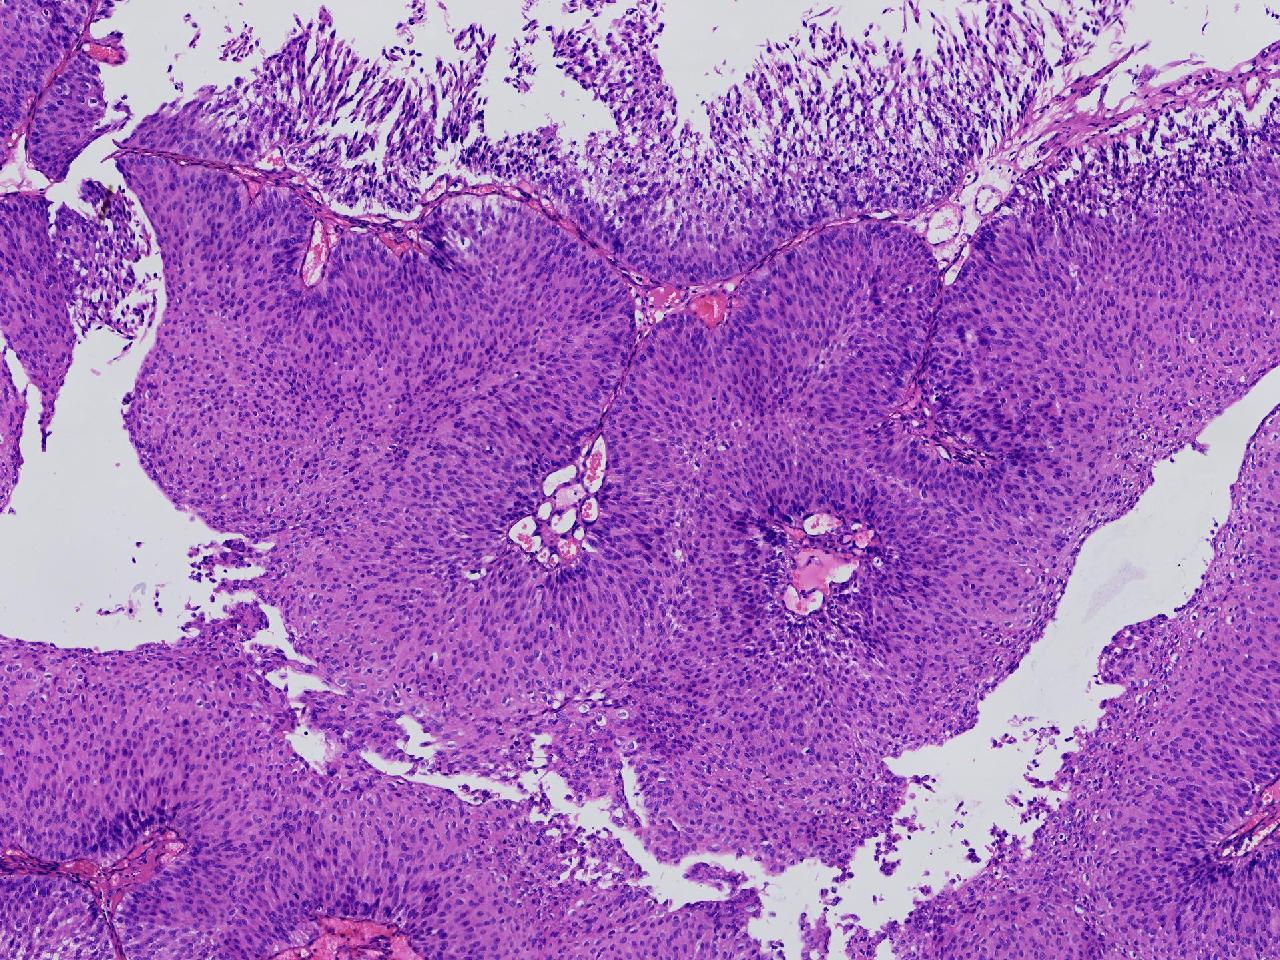

男,79岁,膀胱肿物。

膀胱肿物

灰白色不整形软组织多块,2X1X1厘米。

考虑:乳头状尿路上皮癌

考虑低级别,非浸润。

乳头状尿路上皮癌,低级别。

这几张图片上没有看到明确的浸润。